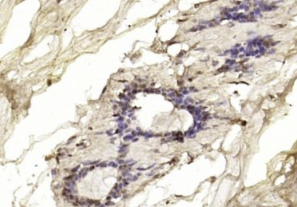

多聚甲醛固定,石蜡包埋(人乳腺癌);用柠檬酸钠缓冲液(pH6.0)煮沸15min后获得抗原;用3%过氧化氢阻断内源性过氧化物酶20分钟;阻断缓冲液(正常山羊血清)37℃30min;用BRCA1抗体孵育。未结合的多克隆抗体在1:200在4°C下过夜,然后根据SP试剂盒(兔子)说明和DAB染色进行操作。